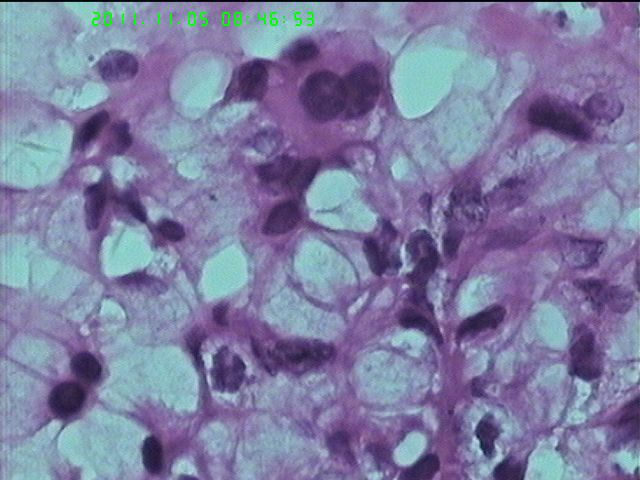

37岁女性患者,左卵巢肿块术中快速:恶性。术后左卵巢囊实性肿块14*9*5CM,灰黄色,部分乳头状,粘液样外观;子宫内膜厚1.5CM;网膜见多个小结节。图1--14左卵巢  15-19网膜  20--23宫腔

粘液腺癌(部分呈低分化)

在图中有明确浸润吗?好像看不出来,但是网膜显示非侵袭性。宫腔图片没有显示浸润。请多上边缘处图像。

请临床查有无阑尾病变,排除阑尾肿瘤转移后,如果没有明确浸润,倾向粘液性*交界性肿瘤伴腹膜种植,肠型。

总之先排除阑尾来源,再看有无浸润,有浸润才打癌。

卵巢粘液性囊腺癌伴内膜及网膜转移。

图1、4、5、6、11中可见疏松组织,网状结构,并见可疑透明小体,加上患者年纪较年轻,卵黄囊瘤不能除外,粘液腺结构可能是卵黄囊中的内胚层成分。且形态上与网膜结节相似。